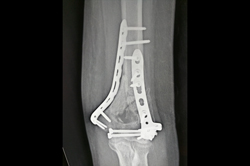

Proximal Tibia